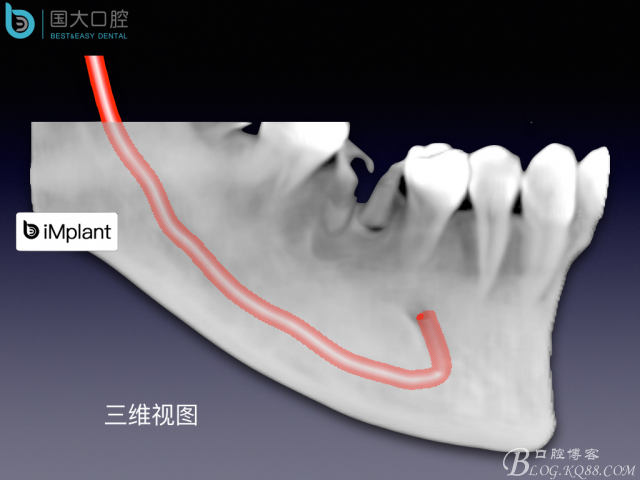

TypeC Socket即刻種植臨床案例

來源于國大口腔 邵現(xiàn)紅醫(yī)生發(fā)表的博文